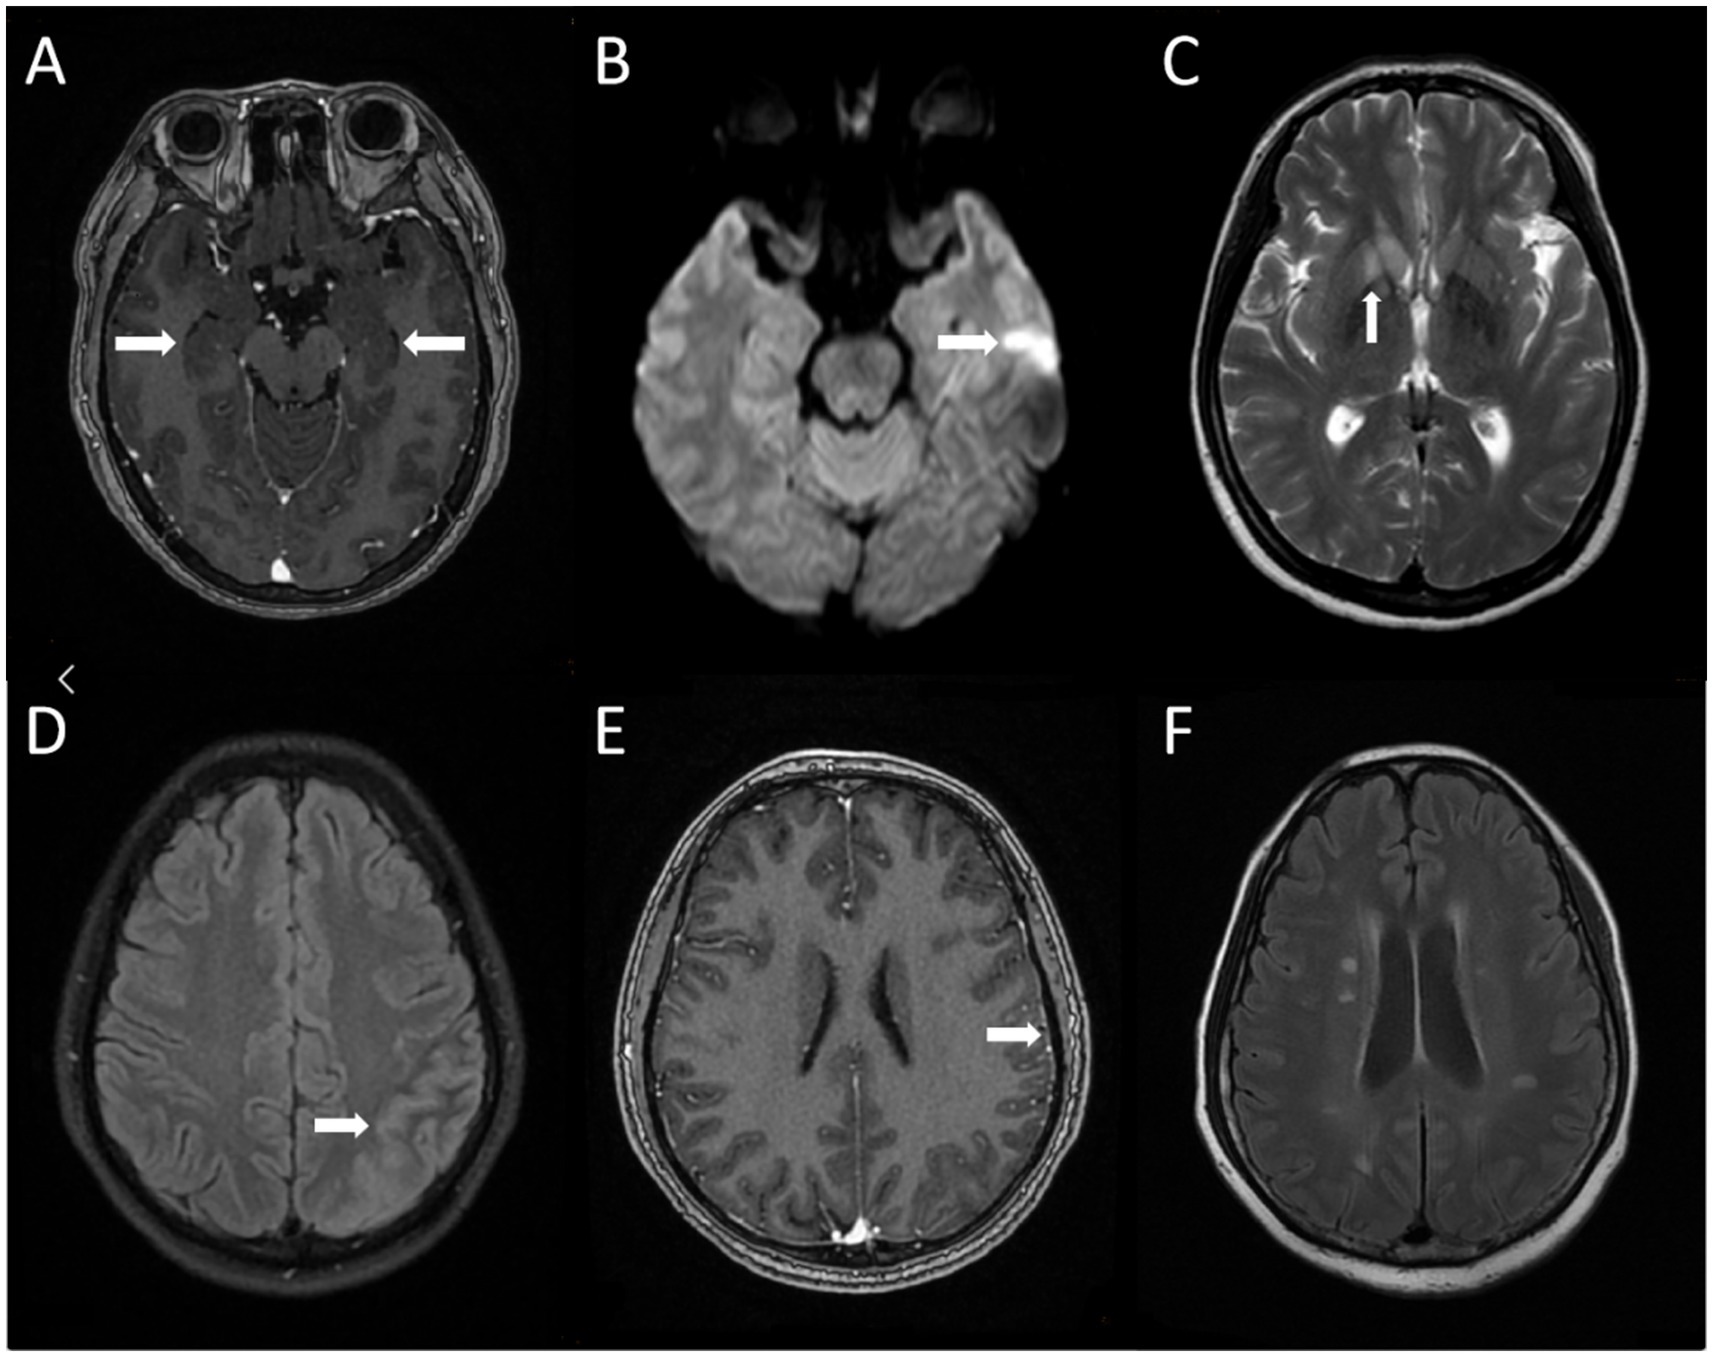

Eighteen cases of AE were examined by MRI, and 9 cases (50.0%) had abnormal MRI findings, which could involve hippocampus (n = 4, 22.2%), insula (n = 3, 16.7%), basal ganglia (n = 2, 11.1%) and frontal lobe (n = 1, 5.6%) (Figure 1).

Figure 1. Brain MRI Characteristics of AE Patients. (A) Brain magnetic resonance enhanced scan in case 9 showed bilateral hippocampal swelling with abnormal signal; (B,C) brain magnetic resonance scan in case 10 showed abnormal signal of left temporal lobe and right basal ganglia; (D,E) brain magnetic resonance plain scan in case 13 showed the left temporal parietal lobe gyrus is swollen and the cerebral magnetic resonance enhanced scan in case 13 showed adjacent meninges are slightly thickened; (F) brain magnetic resonance plain scan in case 14 showed multiple abnormal signals in bilateral corona radiata.